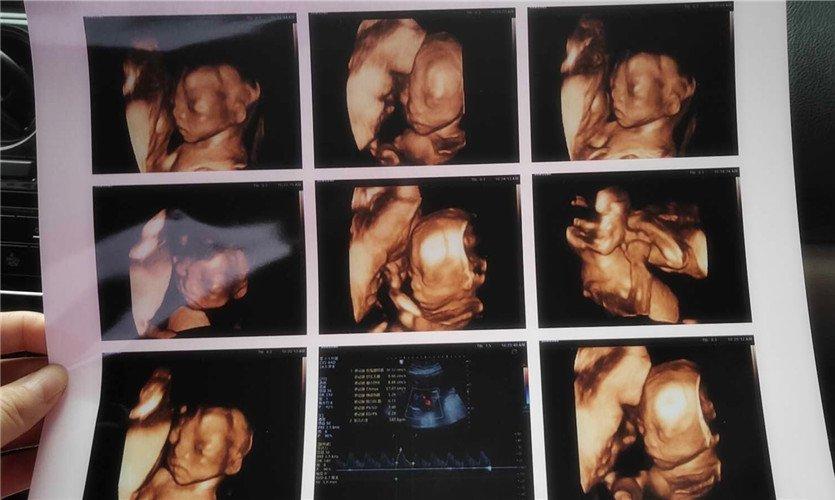

四維彩超是一種先進的醫(yī)學影像技術(shù),通過實時觀察胎兒在母體內(nèi)的活動情況,為醫(yī)生提供了豐富的診斷信息,在四維彩超下,我們可以清晰地觀察到胎兒的蛋蛋(睪丸)的形態(tài)、位置和大小等特征,胎兒蛋蛋是男性生殖系統(tǒng)的重要組成部分,對于胎兒的生長發(fā)育具有重要意義。

在四維彩超下,胎兒蛋蛋呈現(xiàn)出特定的形態(tài)和外觀,通常情況下,胎兒蛋蛋呈現(xiàn)出圓形或橢圓形,表面光滑,內(nèi)部回聲均勻,隨著胎兒的發(fā)育,蛋蛋會逐漸增大,并呈現(xiàn)出明顯的性別特征,醫(yī)生可以通過四維彩超技術(shù),對胎兒蛋蛋的大小、形態(tài)和位置進行評估,以判斷胎兒生殖系統(tǒng)的健康狀況。